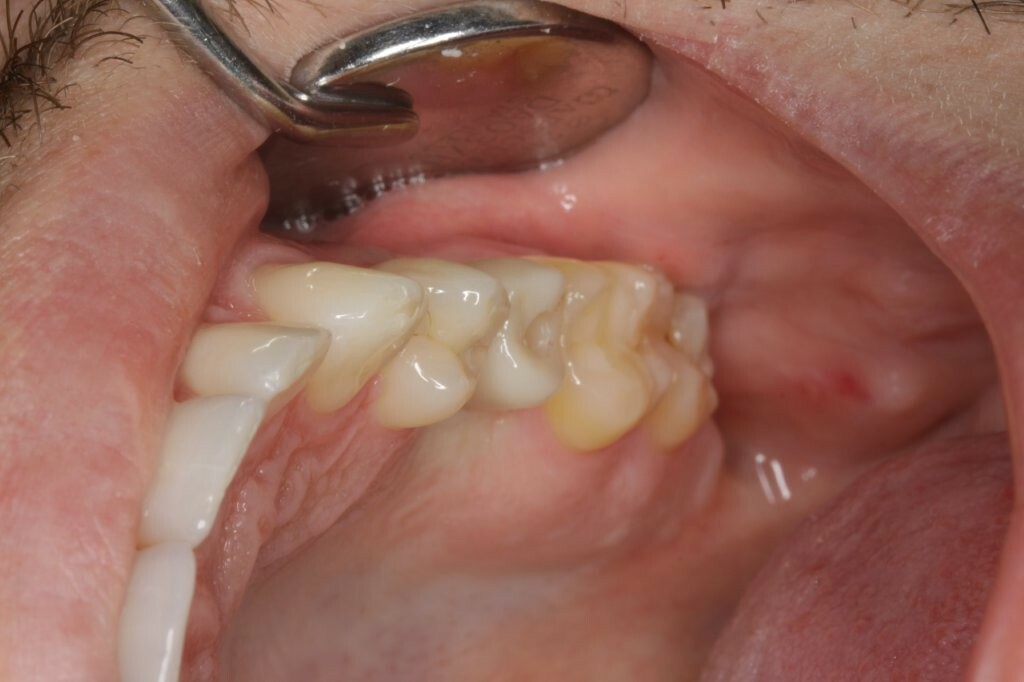

Die Hybrid-Abutmentkrone fügt sich farblich und anatomisch unauffällig in das natürliche Gebiss ein (Abb. 35+36). Auchbei der Nachkontrolle nach zweieinhalb Jahren zeigte sich eine klinisch unauffällige Versorgung, die sich harmonisch in den Zahnbogen eingliedert (Abb. 37-40).